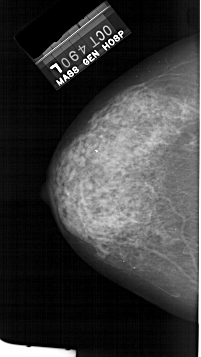

FILE: A_1384_1.RIGHT_CC.OVERLAY

TOTAL_ABNORMALITIES 1

ABNORMALITY 1

LESION_TYPE CALCIFICATION TYPE PLEOMORPHIC DISTRIBUTION SEGMENTAL

ASSESSMENT 4

SUBTLETY 4

PATHOLOGY BENIGN

TOTAL_OUTLINES 1

BOUNDARY